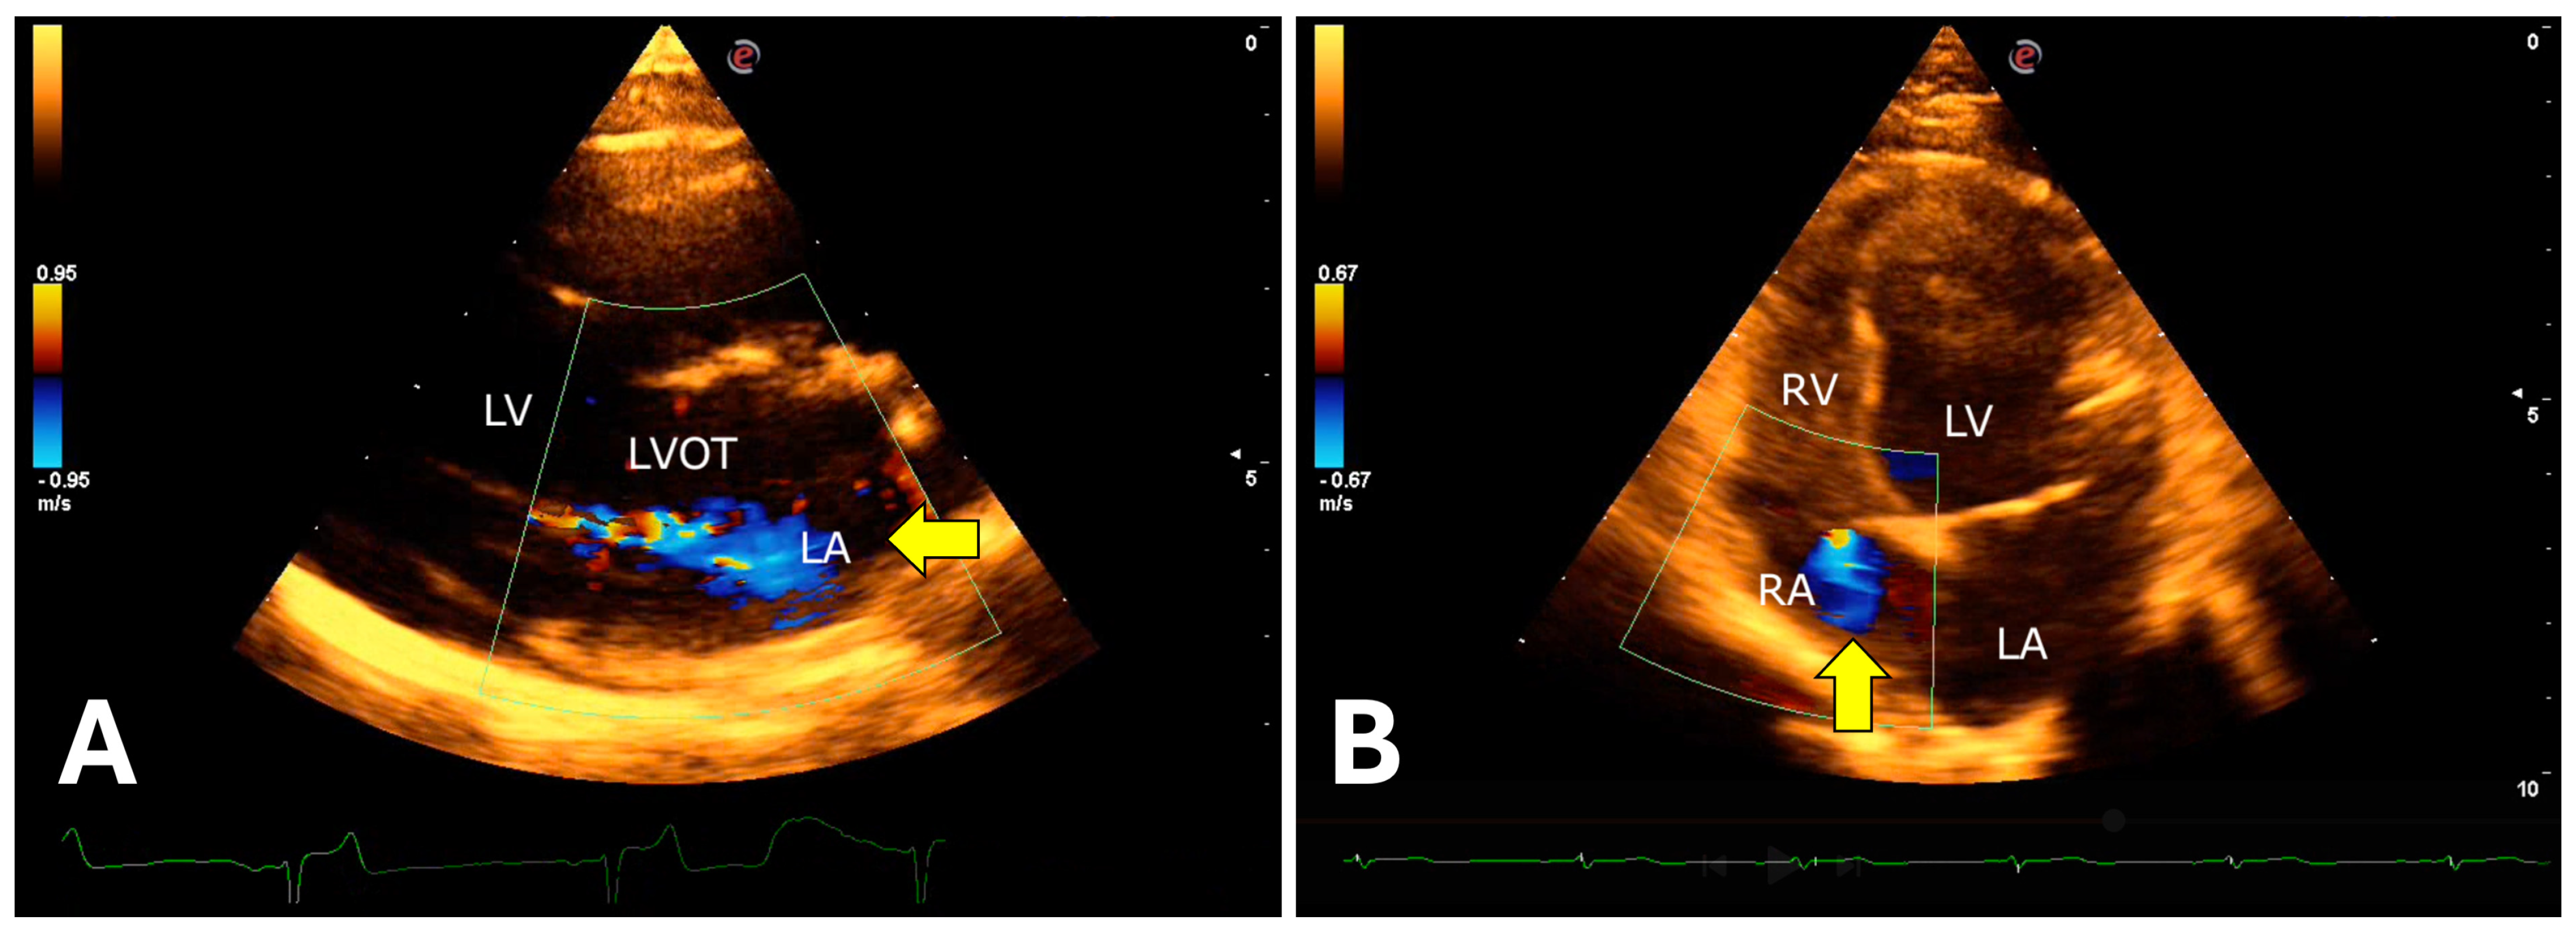

The isovolumetric relaxation time was prolonged, associated with a reduced E wave peak, resulting in a decreased E/IVRT ratio. Color Doppler revealed mitral valve insufficiency (80%), aortic (73%), tricuspid (47%), and pulmonary (13%) in the 15 animals evaluated (Figure 9).

Figure 9. Color Doppler evaluation demonstrating atrioventricular valvular insufficiency in jaguars anesthetized with medetomidine and ketamine. (A): right parasternal window showing turbulent systolic flow in the anterograde direction (arrow) over the mitral valve apparatus. (B): left apical window showing tricuspid systolic regurgitation (arrow). LVOT = Left ventricular outflow tract. LV = Left ventricle. RV = Right ventricle. LA = Left atrium. RA = Right atrium.

The evaluation of cardiac chambers using the echocardiographic technique recommended in dogs and cats by Thomas et al. [28] and Boon [29] is suitable for investigating possible cardiopathies in jaguars. In this study, the application of color Doppler revealed mild mitral and tricuspid valve insufficiency, as well as aortic and pulmonary insufficiency, which have been described in other felids anesthetized with the same protocol [50,51], similar to what is observed in domestic cats [52]. However, Chai et al. [50] did not attribute these findings to the anesthetic protocol itself. The identified valve regurgitations may have a subclinical nature, considering the technical limitations of echocardiographic evaluation in wild felids.